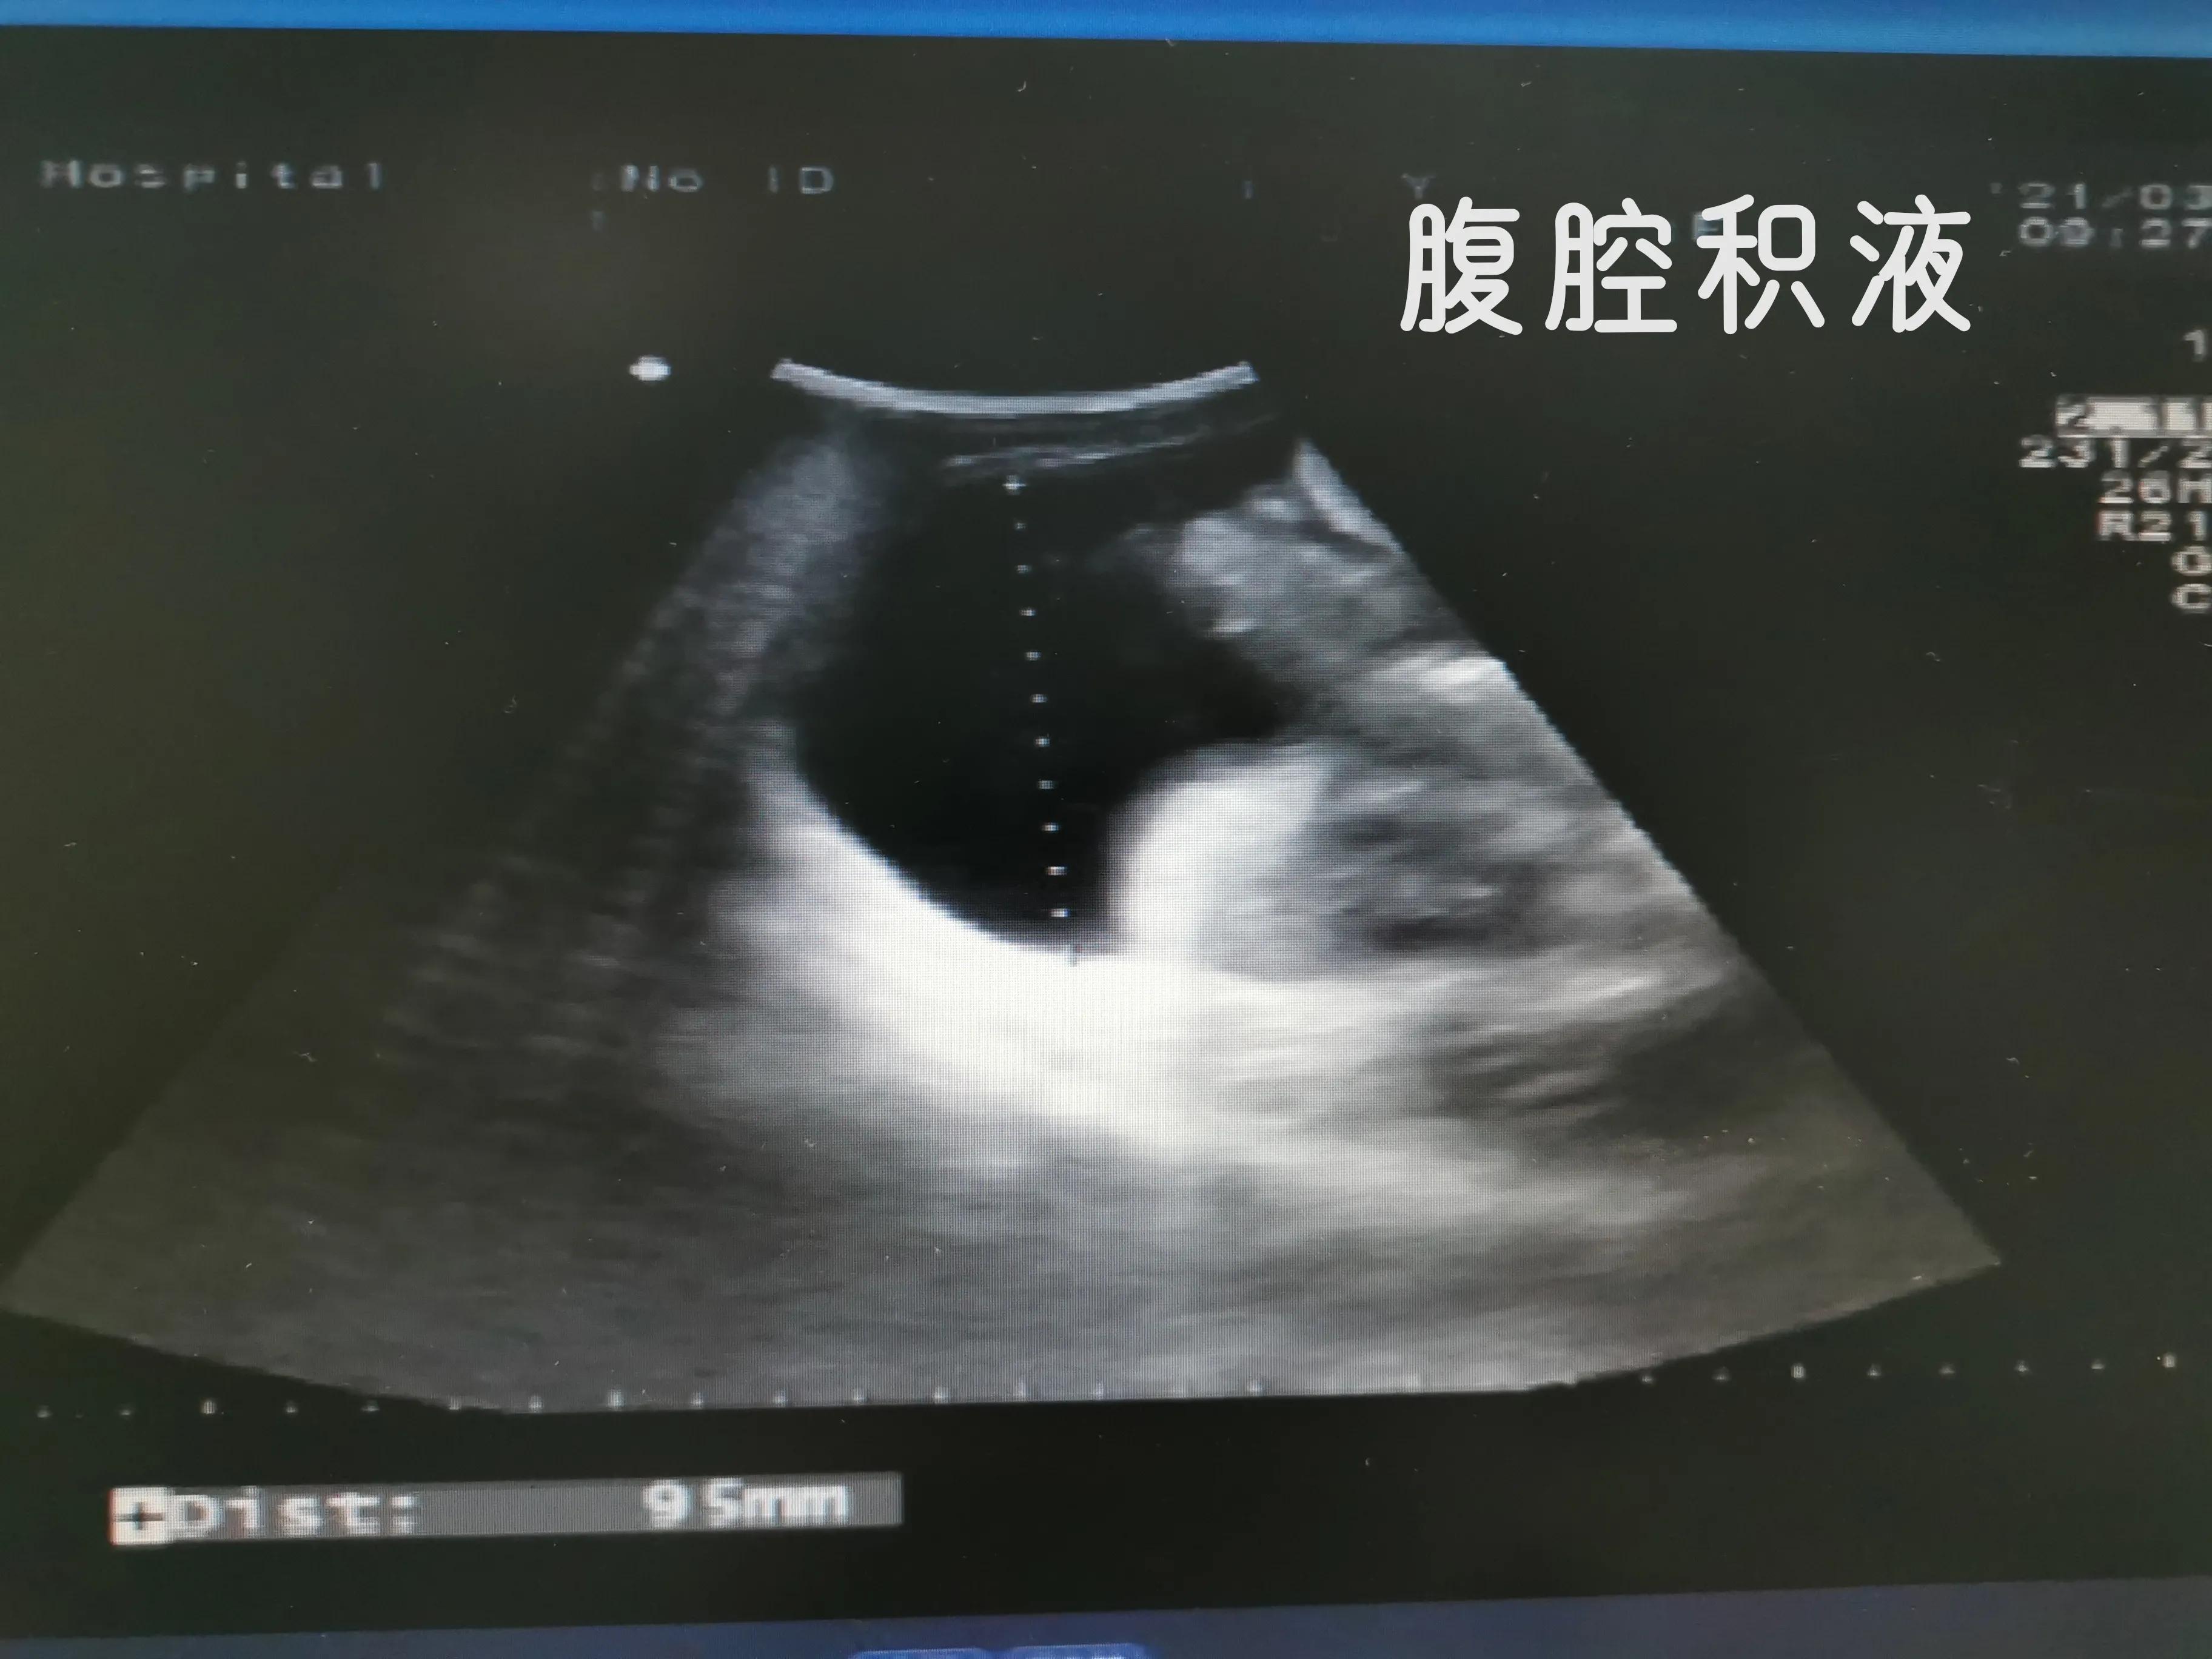

下面我们看看肝硬化失代偿期并肝癌病人肚子里面的情况

肝硬化病人,看起来大腹便便,里面是一肚子水